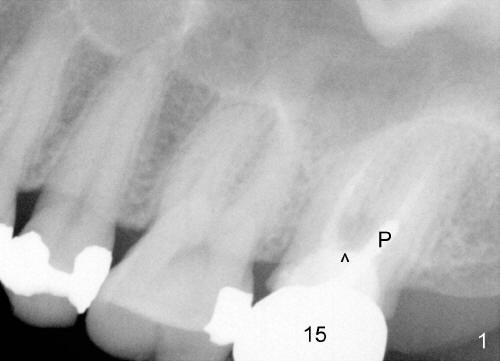

A 42-year-old lady has had problems with the tooth #15 for 4 years. First the crown was dislodged with open margin and furcal lesion (> in Fig.1, P: post; X-ray taken in 2008). Since 2009 (Fig.2,3), the tooth has occasional swelling. The furcal radiolucency remained in the panoramic X-ray (Fig.4 and 4'). Now the patient agrees to have extraction and implant placement.